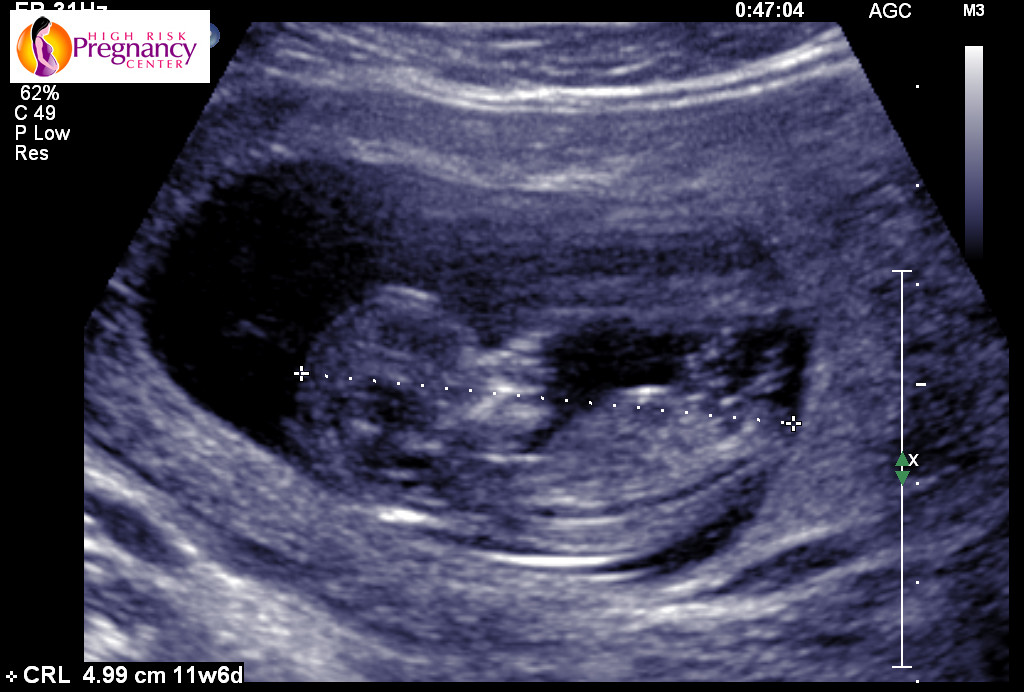

i just had my 12week scan and the tech told me it was still to early to tell but I cant help but think about the gender what do you guys think?!

Attachment 21250

i thought girl as well because of the three lines you see on the first pic. How exciting I will be sure to update once I have my next appointment! :)

Potty shots are no good at all at this stage due to male and females having the same nub. Looking at the second pic I would lean boy seems the nub has lines above it that look stacked but could be cord so could just as easily hear girl too x